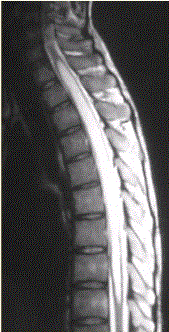

问题 患者女,45岁,胸部不适。影像学检查结果如下图所示。 对病变定位、定性诊断有价值的征象为

选项 A.脊椎增粗 B.邻近蛛网膜下腔变窄 C.病变边界清晰 D.病变特点为一个大囊,其内见一明显强化的结节影 E.病灶内有分隔 F.病灶内可见明显结节样强化

答案 ABCDF